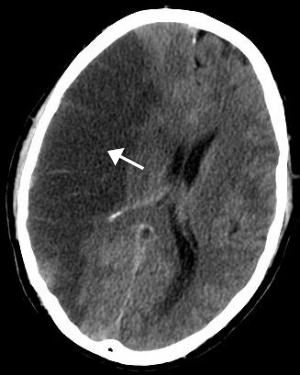

Cerebrovascular disease

| Cerebral angiogram of a carotid-cavernous fistula | |